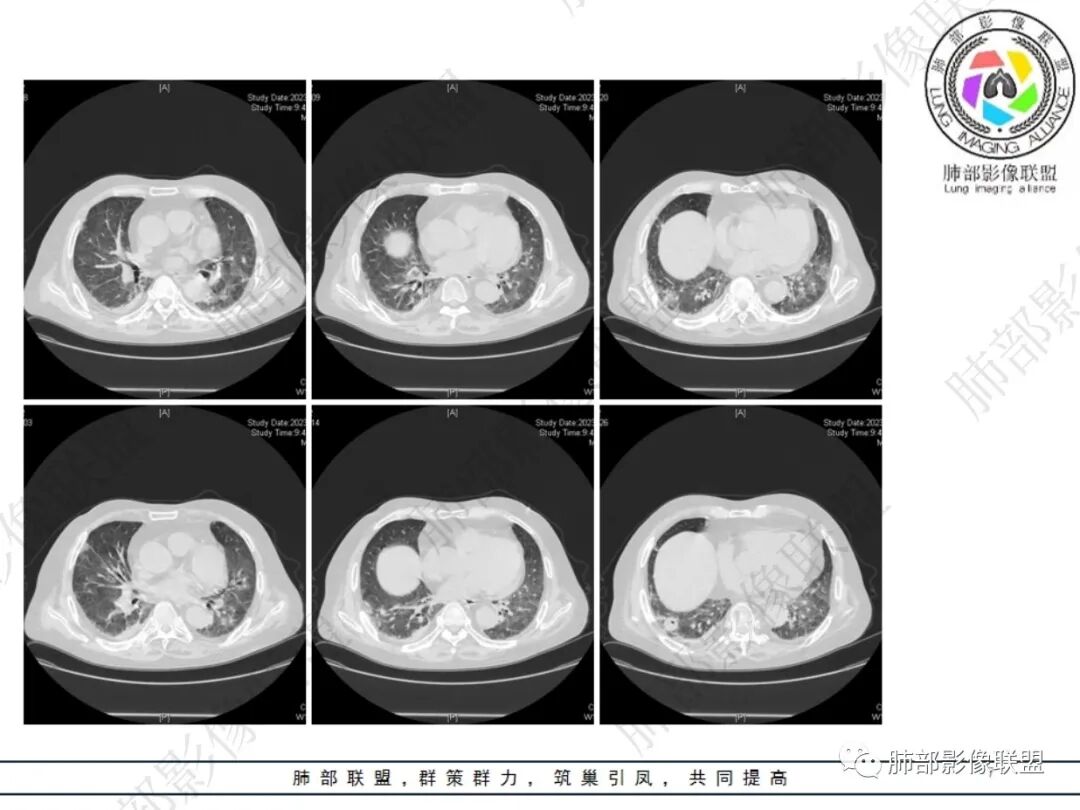

双肺多发结节影,部分靠近胸膜,内有空洞,临床症状不著,病程短,考虑感染性疾病,隐球菌感染?

晨读:两肺多发结节,蘑菇兄弟,晕,空洞,胸膜增厚,隐球,鉴别结核。

晨读 双肺多发散在结节斑片影,边缘部分清晰,密度不均,部分结节内见空洞,外带分布为著。考虑肉芽肿性炎,隐球?血管炎待排。

晨读:两肺叶外周及胸膜下结节及斑块影,大多数病灶边界清,实性强化明显部分病灶干性坏死,环形强化征,坏死轮廓,胸膜下分布特点,蘑菇兄弟,符合肉芽肿性炎,隐球菌感染可能性大,隐球荚膜抗原试验检查。

双肺多发结节及斑片影,外带及胸膜下为主,边界部分清晰,部分病灶内见空洞,强化不显著。考虑感染性病变,隐球菌?

双肺结节灶,周围磨玻璃影,部分病灶见小泡影,胸膜小结节灶,考虑隐球菌感染。